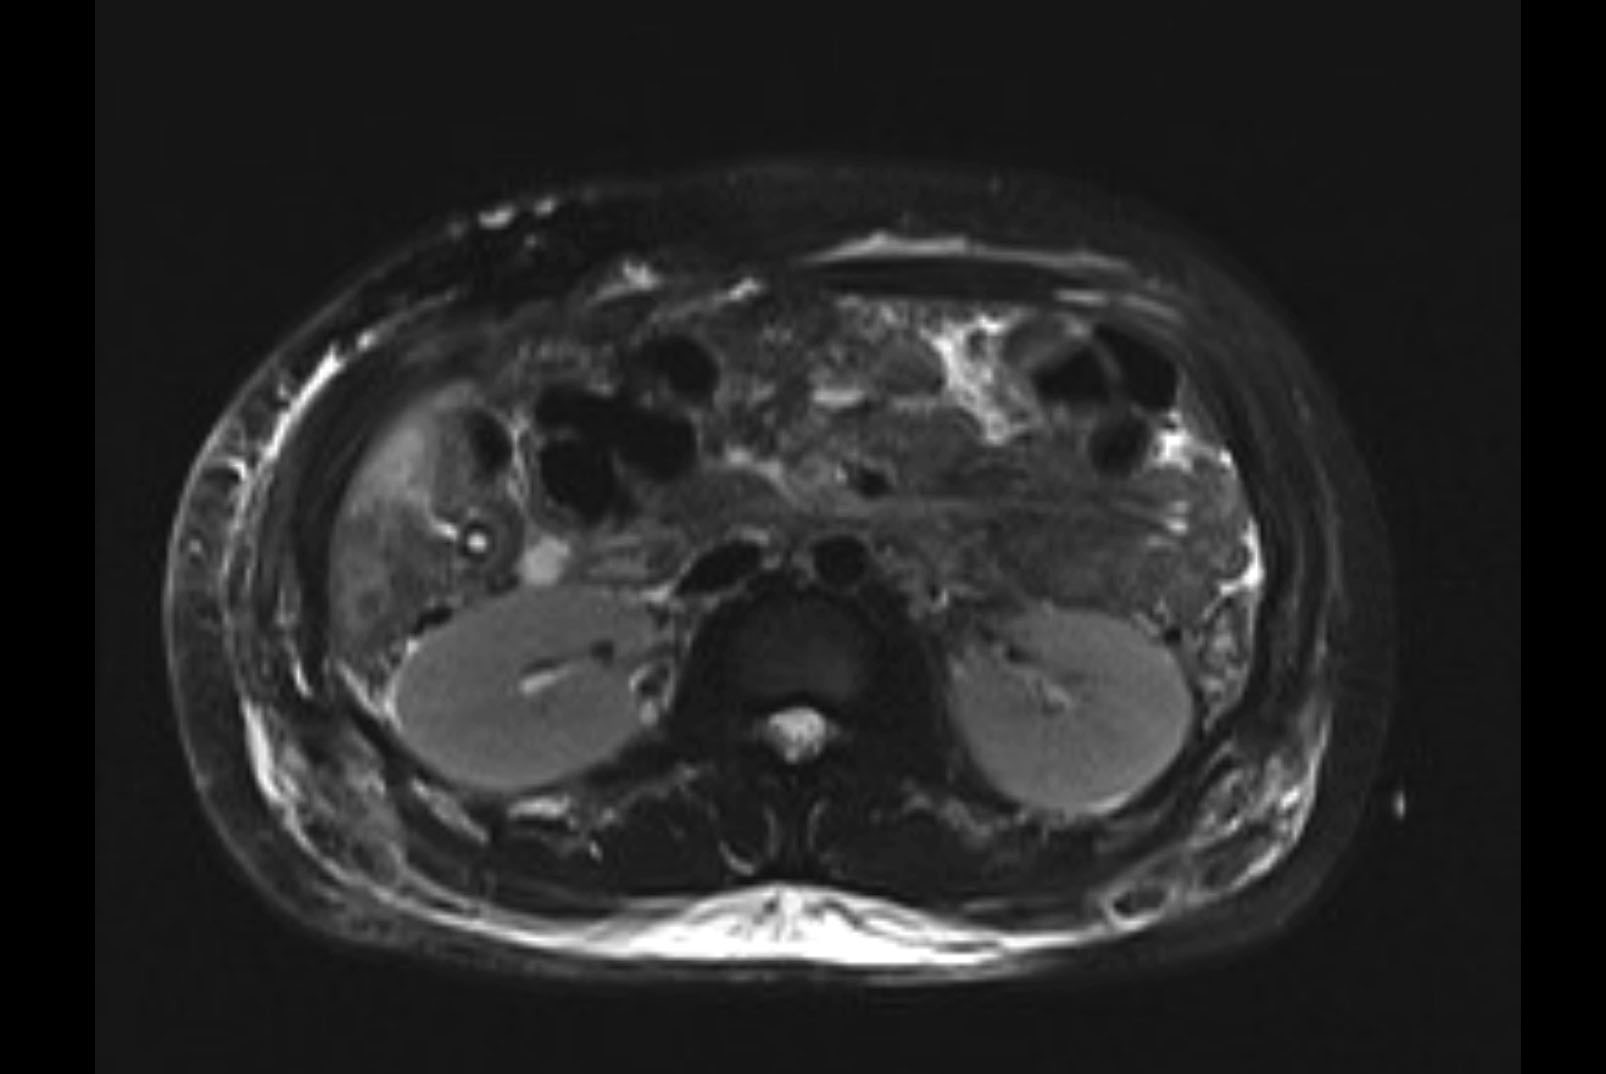

MRI T2